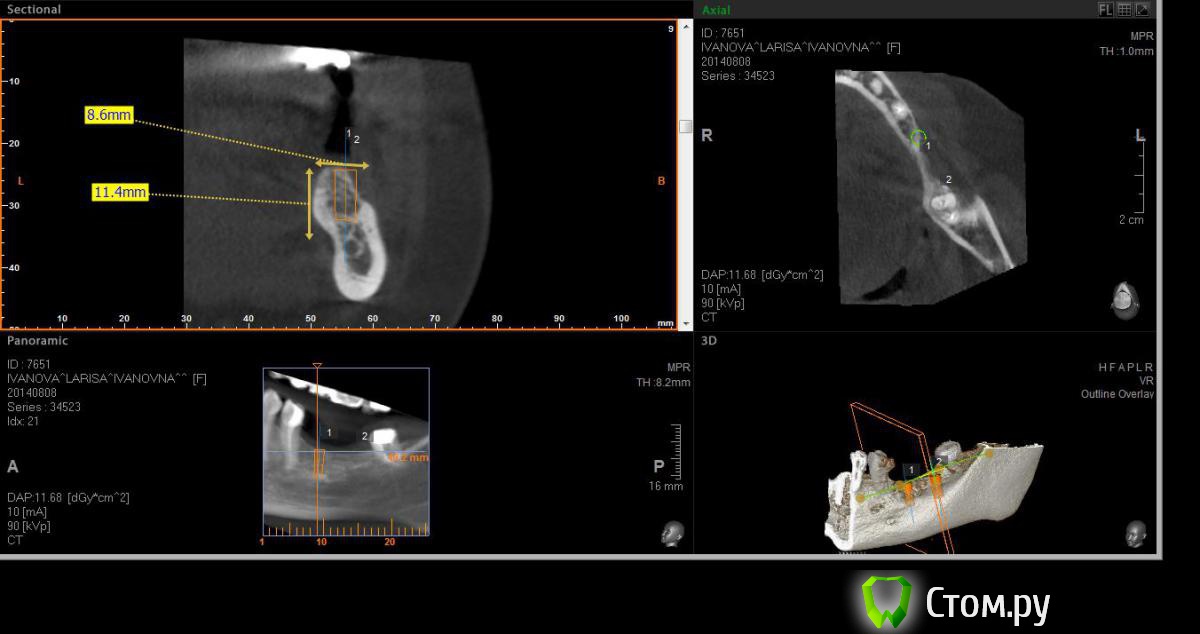

Neilrus Опубликовано 19 августа, 2014 Поделиться Опубликовано 19 августа, 2014 (изменено) Здравствуйте, форумчане-коллеги ) подскажите в очередной раз, пожалуйста.Возник вопрос, для опытных, безусловно, простой, помогите добрым советом.планируем имплантаты в область 36, 37. Длина никак больше 8 не входит, до нерва 10 с копейками и боюсь слишком тонкую кортикалку подязычно оставить.Расщепление из-за формы гребня не думаю, что получится, что-нибудь отломаю точно, хочу поставить как на фотографиях с нкр, голые витки вестибулярно перекрыть еволюшином толстым, припинить весибулярно и язычно если подлезу, либо подошью там.Как вы считаете, рабочая стратегия? Основной вопрос, могу я тут 100% ауто использовать? Объем же не большой, тут со сверления наберу, либо скребочком в зоне операции, заодно и принимающее ложе освежую это же сосидж? ничего не перепутал? И по поводу диаметров, 36 будет 3,75х8, а 37 4,2х8, не кротковаты? Просто у нас только МИС seven пока, либо 8, либо 10 длина. В 37 можно и 5 диаметр поставить, но опять же тонкая язычно остается. По той же причине отказался от длины 10 в 36зубе. Изменено 19 августа, 2014 пользователем Neilrus Ссылка на комментарий

kriokov Опубликовано 20 августа, 2014 Поделиться Опубликовано 20 августа, 2014 Я бы не стал использовать 100% ауто. Может абсолютно все исчезнуть к дню раскрытия.50/50 с Bio-oss. И опять же я не стал бы ставить 8 мм. Мис, зная мисовские цифры для обычной пришеечной резорбции кости. Что останется от 8 мм. после формирователя? И не севен на н.ч.+100, думаю, что если нкр и направление имплантатов на небный бугор, 10 мм может пролезть Ссылка на комментарий

Neilrus Опубликовано 26 августа, 2014 Автор Поделиться Опубликовано 26 августа, 2014 (изменено) +2 )) Во-первых, фиксация у Севена лучше, конечной фрезой на 50 оборотах понемногу наберете ауто. Если есть АСМ или Джилли - еще получите в области ретромолярки. Во-вторых, кости (на самом деле) "немного" больше, чем показывает конусник (это тоже плюс). Поэтому можно и 8, и 10 со стопером или под контролем. Ставьте на 0,5-1 ниже язычной. Выше ставить и обсыпать не рекомендую - разве что только под жесткую мембрану, иначе все уйдет. Язычно я бы не смещался, ставил как запланировано, по шаблону. И в обл. 37 до нерва более 11, так что все будет ОК. Потом придется поработать с мягкими тканями. Удачи!Спасибо. Поставил в итоге два севена десятки, у м4 резьба у шейки никакая по мне так, а шейка тут важна. Наклонил все равно слегка язычно, никуда не провалился, парестезии нет, немного у медиального было ей больно при дотягивании на 25 нютонах, сделал полоборота назад, ауто, потом микс с мр3, эволюшн три пина язычно, два вестибулярно. Швы в пн снимаю, пока полет нормальный, отек уже почти сошел. И по поводу взятия ауто, насколько я правильно понял всех лекторов моих, забор во время бурения только промежуточными сверлами, пилотное и финишное сверление всегда с водой. Нет? Изменено 26 августа, 2014 пользователем Neilrus Ссылка на комментарий